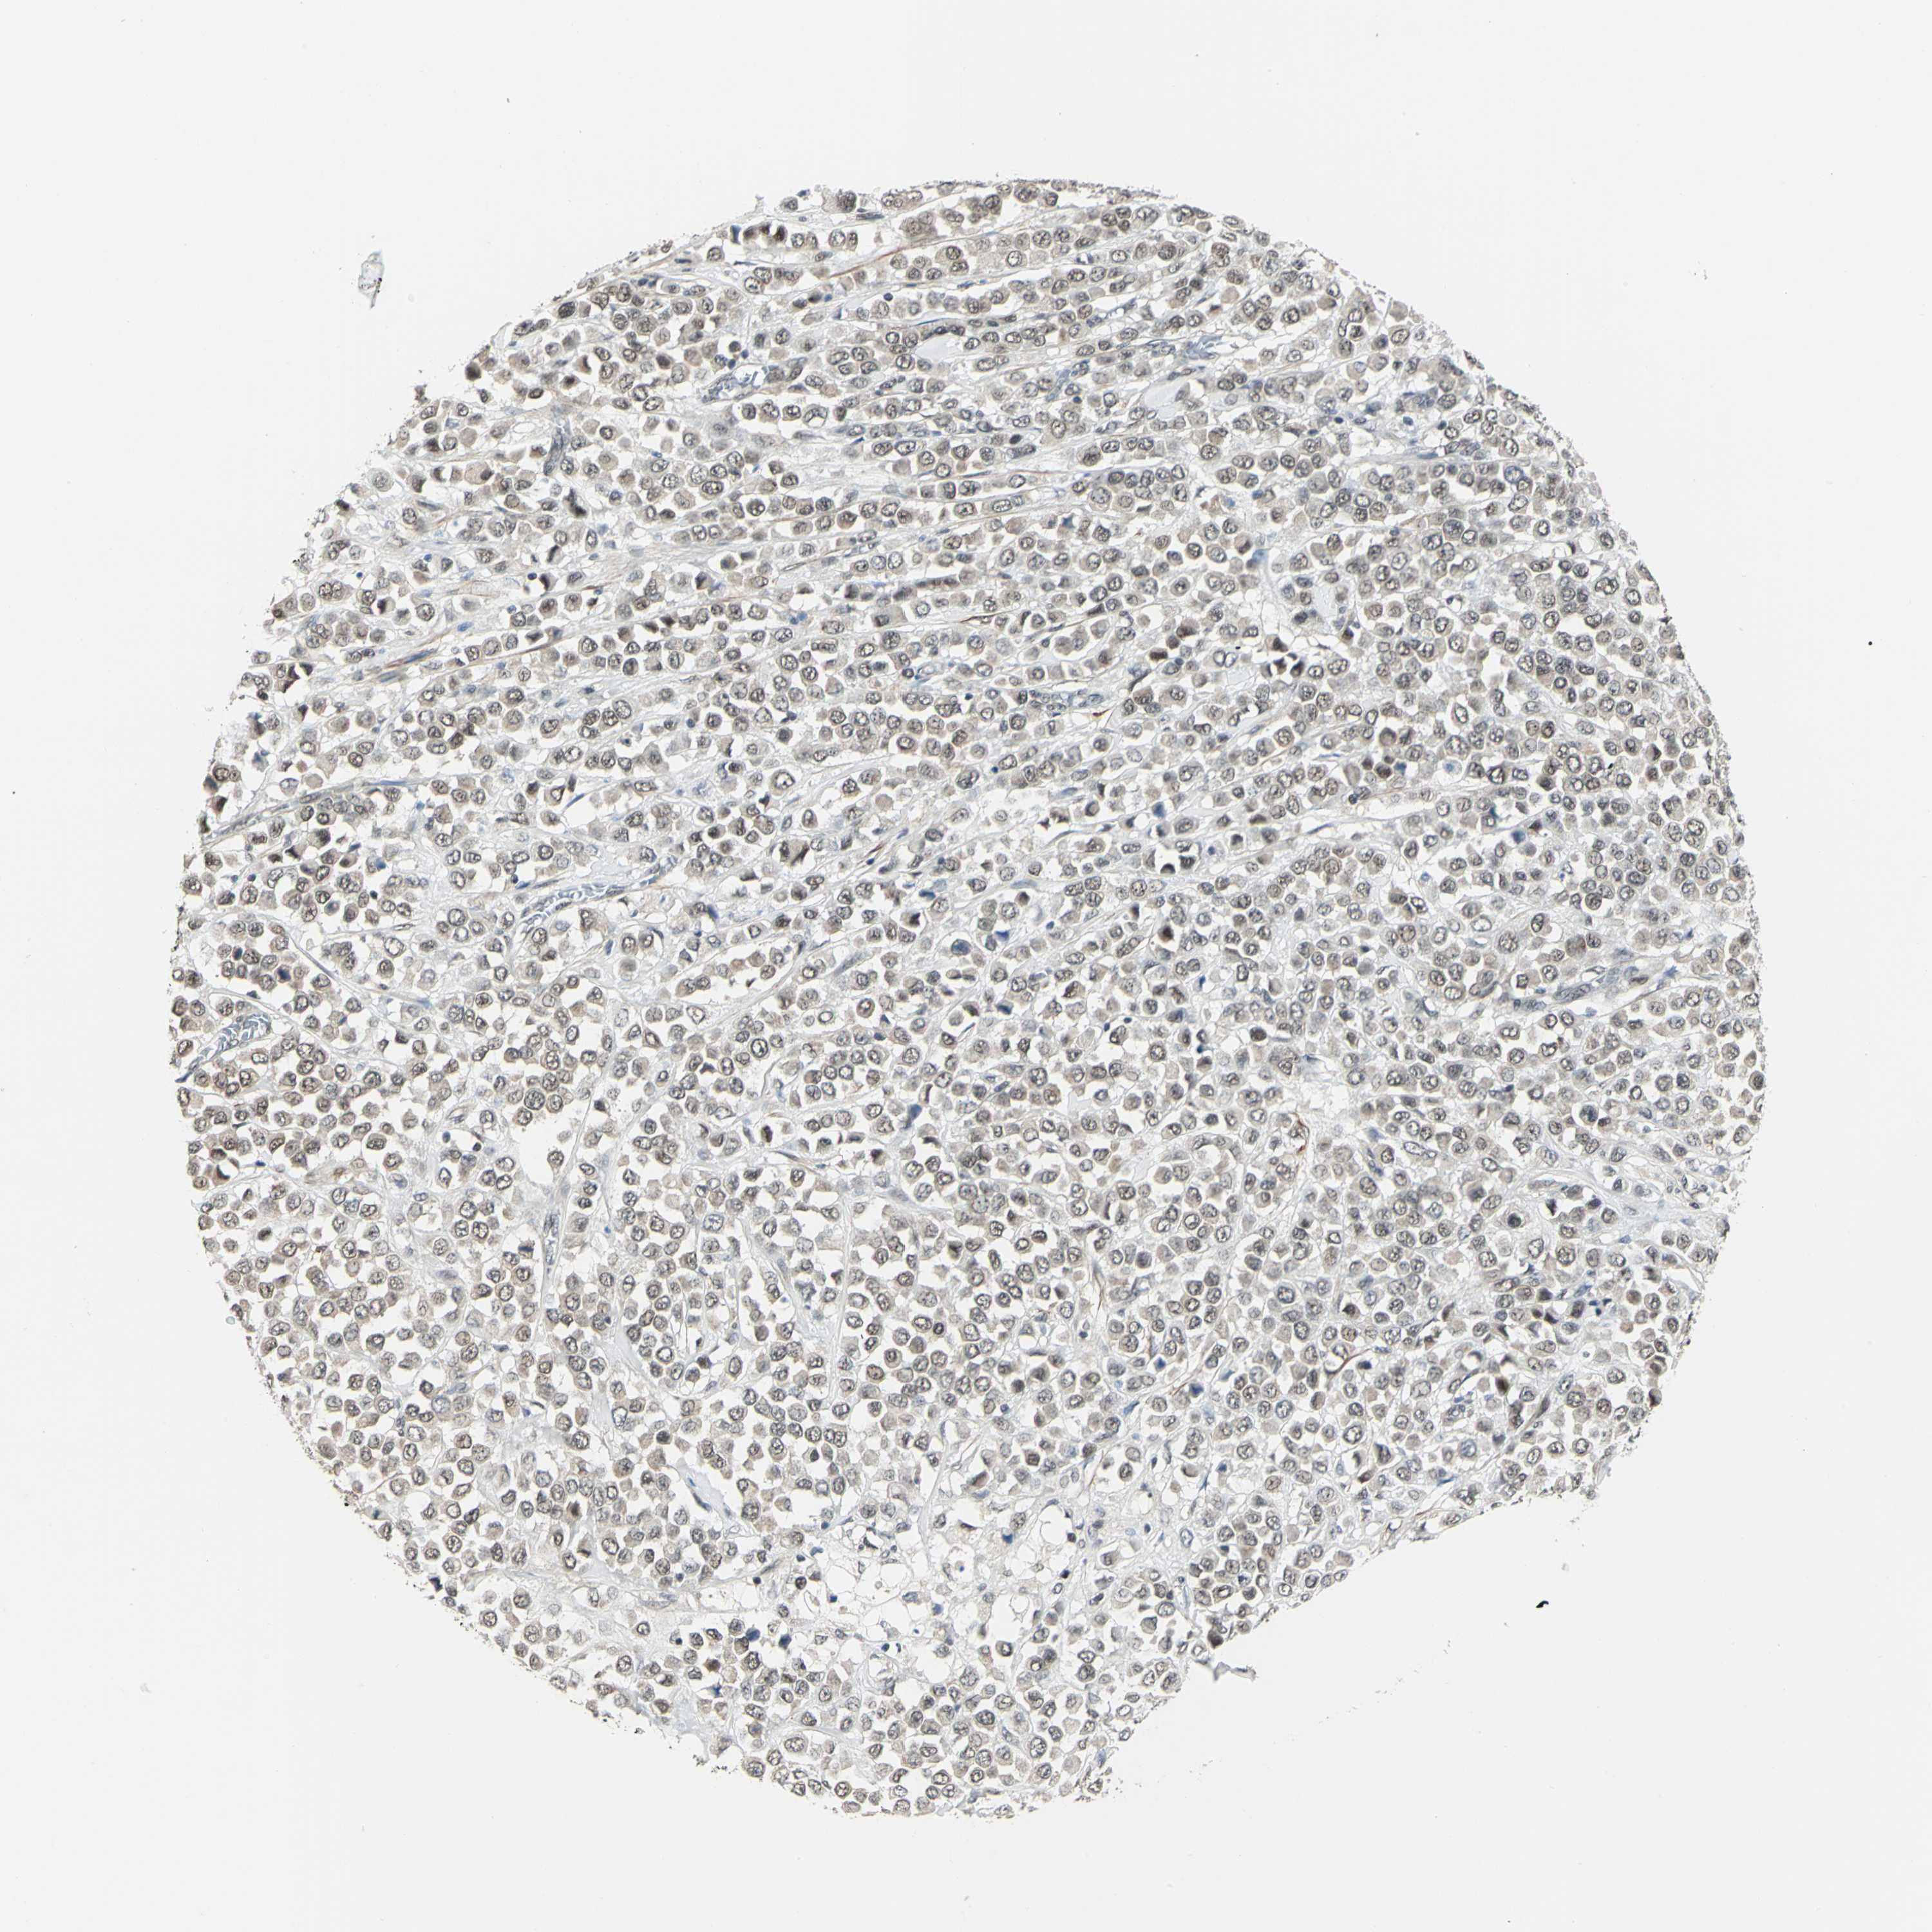

BRCA TCGA BRCA VALIDATION PROTEIN EXPRESSION